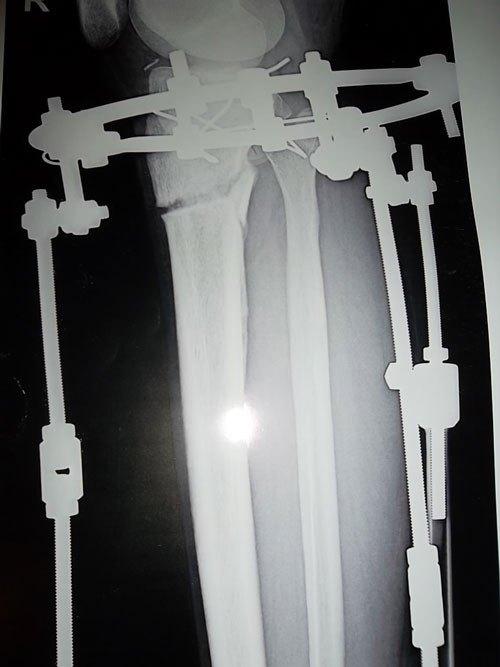

Сообщение Sekretar Onipko »

8 дней круток.

SAM_4062.JPG